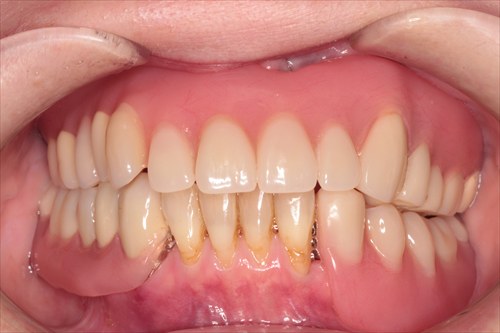

術後です。

それでも「今までの人生で一番かめる!」とおっしゃっていただけました!